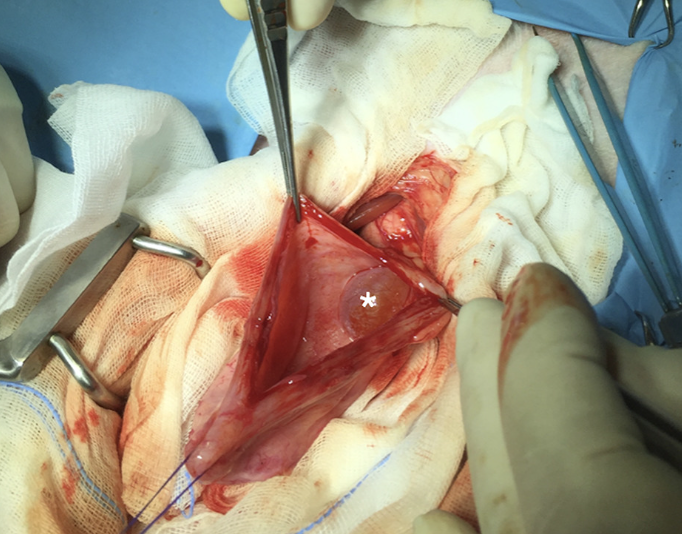

방광을 열어서 보면

이런식으로 방광내부에 물주머니처럼 보일 수 있다.

요관의 폐색문제가 유발될 경우 수술을 하기에 반드시 개통성에 대한 체크가 무엇보다 중요한 경우.